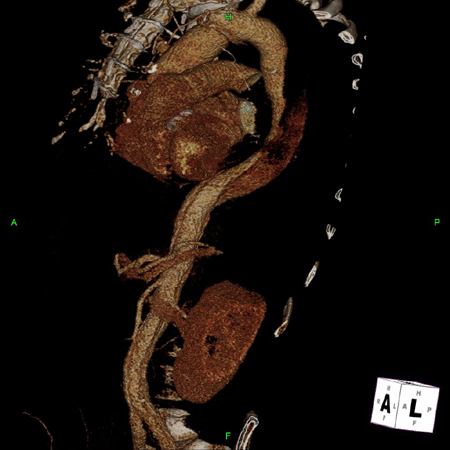

3D CT, distal dissection

From the collection of Dr Eric E. Roselli; used with permission